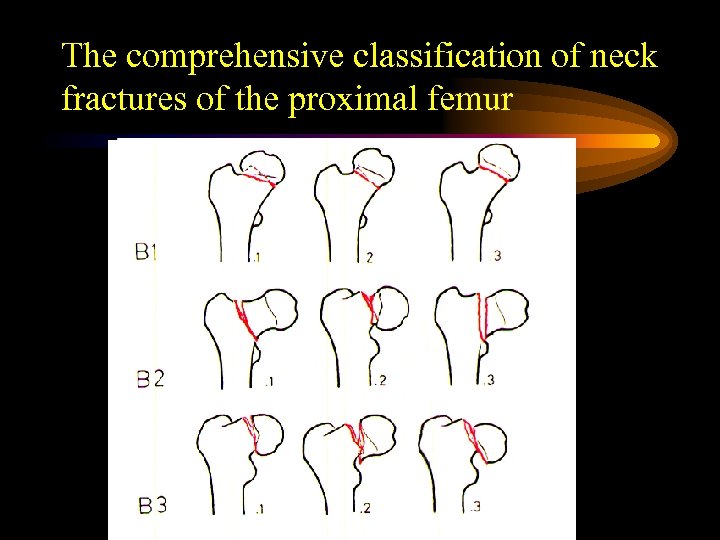

The comprehensive classification of neck fractures of the proximal femur

The comprehensive classification of neck fractures of the proximal femur